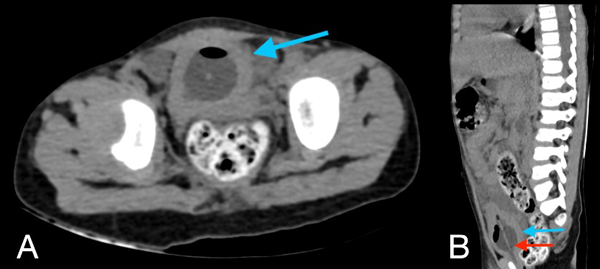

En la tomografía se evidenció presencia de S1-S2 con ausencia del resto de cuerpos sacro-coxígeos, así como hipodensidad a nivel de la médula que podría sugerir siringomielia (Figura 1). También se encontró falta de unión de algunos elementos posteriores a nivel de L5-S1 (Figura 2), lo que sugiere el diagnóstico de síndrome de regresión caudal asociado a probable siringomielia y probable vejiga neurogénica dado engrosamiento marcado de las paredes vesicales (Figura 3). Además, se encontró dilatación ureteropielocalicial de forma bilateral (Figura 4). A raíz de estos hallazgos, se solicitó una valoración por genética clínica, la cual determinó que la paciente cumple con los criterios clínicos de regresión caudal y tiene antecedentes de diabetes gestacional insulino-dependiente, lo cual es un factor de riesgo.

Figura 3. Tomografía de abdomen, cortes axiales, donde se muestra dilatación de la pelvis renal derecha (A), e izquierda (B), así como de los trayectos ureterales hasta distal y discreto engrosamiento de sus paredes (C, flecha azul derecho, flecha roja izquierdo).

Figura 4. Tomografía de abdomen en corte axial (A) y sagital (B): la vejiga evidencia engrosamiento concéntrico de sus paredes de aproximadamente 7,4 mm (flecha azul en A y B), con la presencia de balón de sonda Foley en su interior (flecha roja en B).

En este caso, se encontró una ausencia parcial sacro coxígea con preservación de S1 (Figura 1), asociada a no unión de elementos posteriores de L5 y S1 (Figura 2), siendo un síndrome de regresión caudal tipo I según Pang, asociado a alteraciones genitourinarias dadas por hidronefrosis bilateral (Figura 3) y engrosamiento de las paredes vesicales (Figura 4).